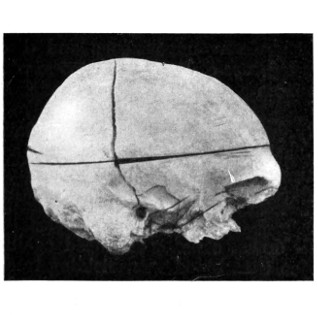

43 A and B. An explosive fracture of the vault of the skull 113

44. A temperature chart illustrating the changes in temperature observed in head-injuries 117